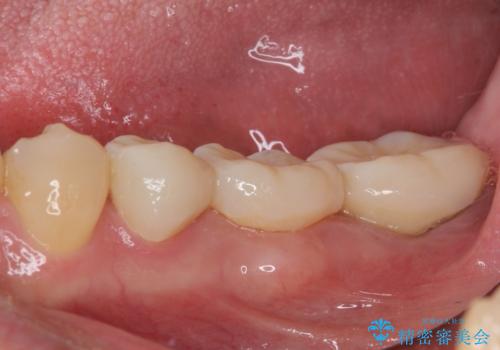

- 近医にてブリッジ治療を行った歯が痛くてたまらないとのことで来院された患者様です。

診察を行ったところ、奥の土台になっている歯は神経組織が失活しており、根尖部に病変があり、そこが原因で痛みを生じている状態でした。

根管治療を行うためにブリッジを除去したところ、むし歯が歯肉の奥深くにあまで及んでいたため、歯周外科処置によりむし歯が歯肉縁より浅い位置へと改善することとしました。